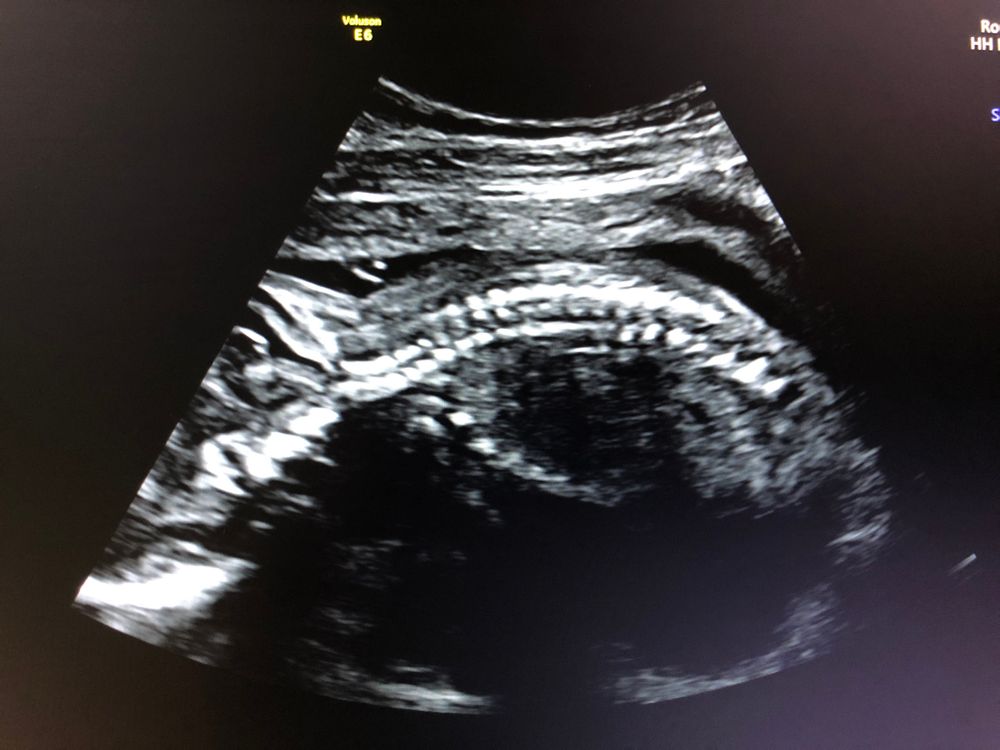

Срок по УЗИ 23,3. Из заключения: поперечное положение, 2 позиция, передний вид, плод расположен высоко. Где на снимке головка, куда «смотрит» ребенок, почему визуализируются два позвоночника. И ещё интересно - как правильно смотреть снимки УЗИ - они в зеркальном отражении или может быть вверх тормашками? Спасибо.

в норме позвоночник состоит из позвонков с тремя точками окостенения - поэтому тоже может сложиться впечатление, что несколько «позвоночников».

ниже прикреплю снимки абсолютно «нормальных» спинок😌 специально сохранила примерно в таком же положении как у Вас

УЗИ показывает, как есть. Ваш малыш на данном снимке(в момент проведения УЗИ) лежит личиком вниз, голова справа. Почему два позвоночника то? )))) Это один. На этом сроке плод ещё во всю крутится в матке, размер позволяет.